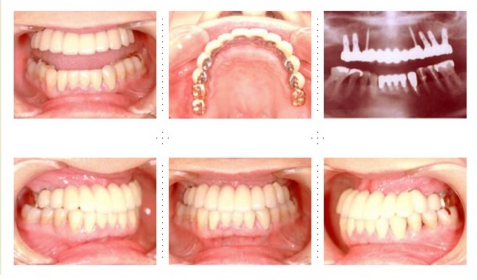

症例1

58才 女性

嘔吐反応が激しく入れ歯を入れると気持ち悪くなってしまうと、インプラント希望で来院されました。

上顎左右奥に4本ずつ計8本のインプラント埋入。下顎左右奥に3本ずつ計6本のインプラント埋入上下顎とも全体的にセラミックを使用した冠をセット。